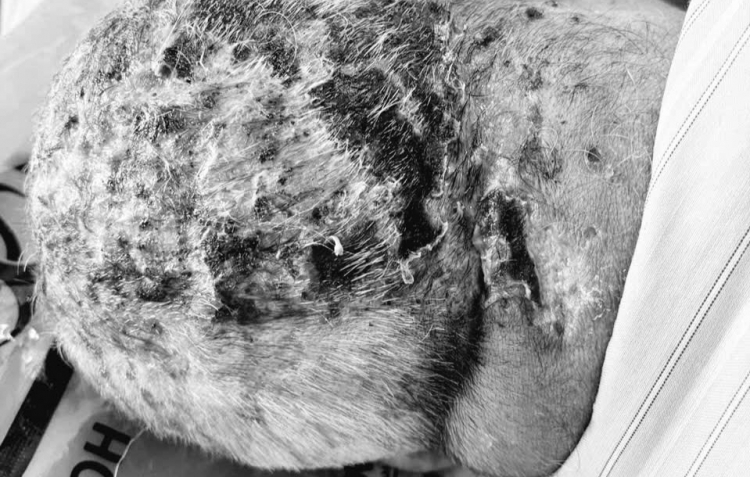

Vùng đầu của bệnh nhân bị viêm loét, chảy dịch nghiêm trọng sau khi đắp lá kín đầu - ảnh: T.S

Trước đó, cụ ông L.V.K. ( 88 tuổi, ở Hà Nội) nhập viện trong tình trạng co giật liên tục, la hét, co cứng cơ vùng đầu – cổ. Trên đầu bệnh nhân có nhiều vết loét rộng, chảy mủ.

Từ ngày 3-8/10, cụ K, đắp lá 2 lần kín đầu. Không lâu sau, cụ lên cơn co giật, hoảng loạn, gia đình lại đưa ông vào nhập viện.

May mắn, sau 3 ngày điều trị tích cực, vết thương đã se lại, tiến triển tốt hơn. Khi ổn định, bệnh nhân sẽ được chuyển đến chuyên khoa ngoại để tiến hành cắt bỏ phần tổn thương bị hoại tử sau gáy, vệ sinh vết thương và loại bỏ phần lá bám sâu vào da đầu.